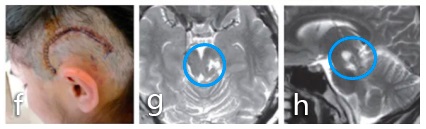

手术入路和体位:c图表示半坐位进行了手术,通过左侧小脑上天幕下入路全切肿瘤。d图显示整个外侧枕骨区域暴露在下,直到滑车神经出口(箭头所示)。e图表示脑干的进入点选择在上丘脑的侧面,然后的肿瘤切除腔约6mm

术后:f、g图术后MRI影像显示肿瘤得到了全切。患者无并发症,无其他神经系统缺陷。术后病情平稳,术后5年内无肿瘤复发。